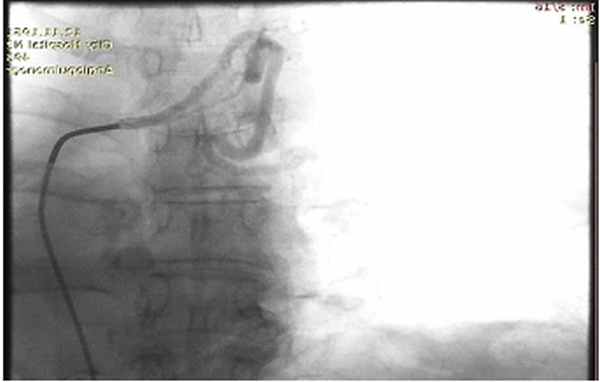

Патологически расширенная правая бронхиальная артерия

Учитывая вышеуказанное, диагностика легочного кровотечения, как правило, требует выполнения ригидной̆ бронхоскопии, позволяющие не только минимизировать риск развития асфиксии, но и выполнить ряд лечебных мероприятий. Выполняемая при ригидной бронхоскопии клапанная бронхоблокация позволяет добиться надежного временного гемостаза и практически полностью исключает риск развития фатальных осложнений.В случаях легочного кровотечения большего объема (2-3 ст.) выбор лечебной тактики зависит, как правило, от основного заболевания. Источником кровотечения из большого круга кровообращения служат бронхиальные артерии, являющиеся основой артериального кровоснабжения легочной паренхимы.

Видеоторакоскопическая расширенная комбинированная бронхопластическая лобэктомия у пациента с центральным раком левого легкого, осложненного легочным кровотечением Обычный диаметр этих артерий менее 1 мм. Любые визуализируемые по данным Ангио-КТ бронхиальные артерии могут считаться патологически расширенными. При легочных кровотечениях любого объема, с наличием патологических бронхиальных артерий, рентгенэндоваскулярные вмешательства могут быть методом выбора как дополнительной диагностики, так и радикального гемостаза.

Непосредственным методом гемостаза является эмболизация бронхиальных артерий. По данным литературы эффективность рентгенэндоваскулярной эмболиации бронхиальных артерий составляет около 97%.